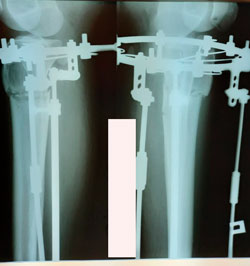

Re: Фаризат

Сообщение Sekretar Onipko »

на фиксации

Вложения

image-10-11-20-02-28-2.jpg

image-10-11-20-02-28-5.jpg